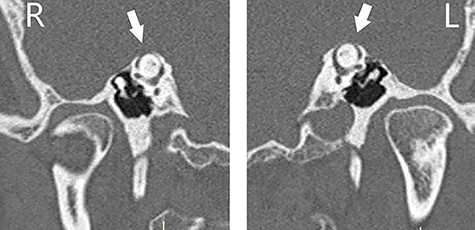

Otoscopic examination was bilaterally normal with no evidence of haemotympanum. At 512 Hz, Weber test lateralized to the right, where Rinne test was found negative. Facial nerve function was normal. An initial audiogram (Fig. 1) demonstrated right severe mixed loss with a maximal air-bone gap of 50 decibel (dB) at 500 Hertz (Hz). There appeared to be a background of bilateral symmetrical high-frequency sloping sensorineural loss, in keeping with presbycusis. Tympanometry was bilaterally type (A). A temporal bone HRCT scan with reformatting in Pöschl and Stenvers views was performed and SSCD was found bilaterally (Fig. 2). Ossicular chain, mastoid cells and the rest of the temporal bone were all normal. There was no radiological evidence of ossicular chain disruption. Mastoid cells and the rest of the temporal bone were all normal.

CT scan of the temporal bones of the patient, and images were reformatted in the planes of the right (R) and left (L) SSCs (Pöschl view); bilateral dehiscence (arrows) is noted.